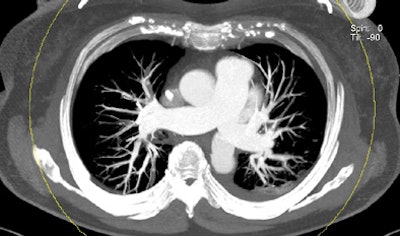

| Patient with bilateral segmental and subsegmental PE and large perfusion defects on dual-energy iodine distribution maps. All images courtesy of Dr. Ralf Bauer. |

Dual-energy CT enables the selective display of iodine distribution within the pulmonary parenchyma following contrast-enhanced pulmonary CT angiography, which in turn permits the calculation of perfusion defect (PD) size in patients with suspected PE.

The researchers measured perfusion defect size in the lung parenchyma caused by PE on dual-energy iodine distribution maps, and expressed it in two ways: as absolute quantification (VolPD in mL) and relative to the total lung volume (RelPD in %).

Signs of right heart strain were determined using multiplanar reconstructions in a cardiac four-chamber view. Patient records were searched for D-dimer, pO2, and pCO2 levels at admission; echocardiography signs of right heart strain; and information on readmission for recurrent onset of PE and death.